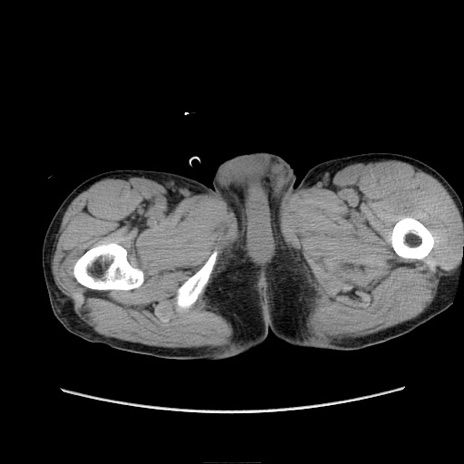

症例11(横断像)

【症例】 60歳代男性

【主訴】 下腹部痛

【現病歴】 本日夜中より下腹部痛の症状認め、受診。

【既往歴】 膀胱癌(膀胱全摘+尿管皮膚瘻術) 、胃癌術後

【身体所見】 BT 35.3℃、PR 58/min、BP 136/98mHg、腹部平坦、軟、腸蠕動音±、ストマ留置あり、左上腹部~正中部に圧痛あり、反跳痛なし。

【データ】WBC 5100、CRP0.01